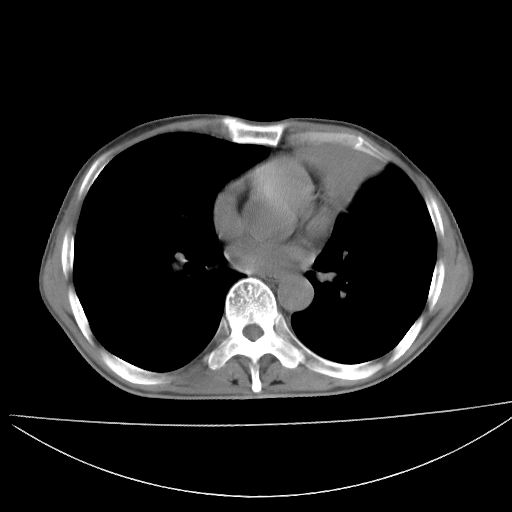

以下是引用杀毒软件在2009-4-28 17:58:00的发言:[br]考虑----左肺慢性肺脓肿形成继发上叶含气不良---抗炎后复查---待排肿瘤所致[br][br][本贴已被 杀毒软件 于 2009-4-28 18:01:26 修改过]